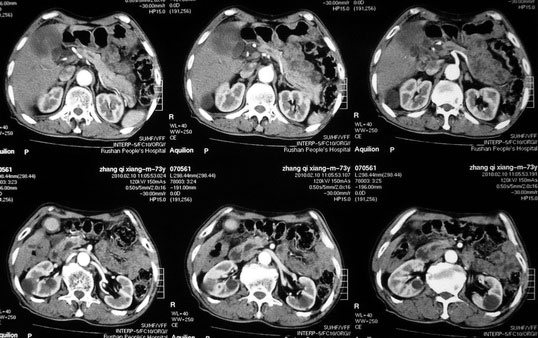

肝胆管细胞癌

患者AFP正常,无肝病病史。CA199 1000ng/ml,CEA偏高。血象WBC正常,N偏高。

化脓性胆囊炎累及肝脏;胆管细胞癌;肝转移瘤

活检病理

:是

胆管细胞癌

。

这个病人开始就是主要鉴别的肝脓肿和胆管细胞癌。可是增强后环征也不明显,占位内造影也非常不明显。这种情况怎么判断?谢谢大家。

病灶强化幅度较轻,低密度坏死区内见无定形高密度影,是其特点。